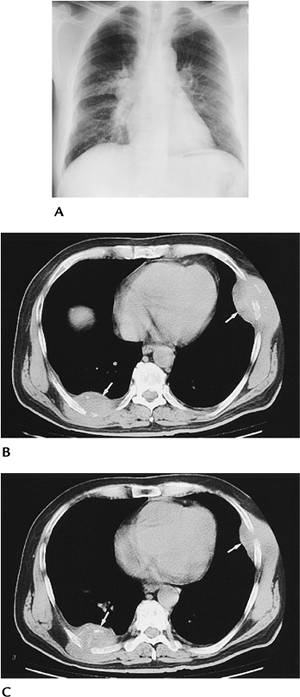

P.774

FIGURE 11-14 Tuberculosis with rib destruction and chest wall abscesses. (A) Chest radiograph showing a right perihilar infiltrate and adenopathy. (B,C) CT images showing chest wall abscesses with rib destruction (arrows).